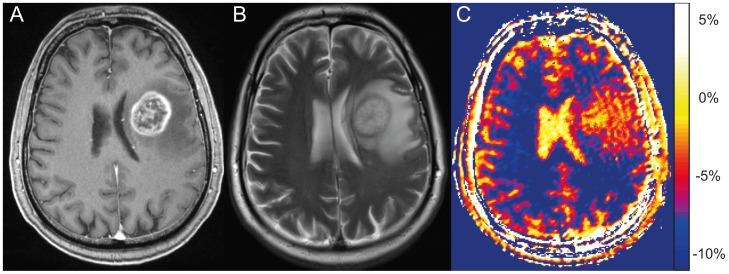

Twelve patients with newly diagnosed histologically proven glioblastoma were enrolled in this prospective ethics committee-approved study. NOE mediated CEST contrast was acquired with a modified three-dimensional gradient-echo sequence and asymmetry analysis was conducted at 3.3 ppm (B1 = 0.7 µT) to calculate the magnetization transfer ratio asymmetry (MTR(asym)). Contrast enhanced T1 (CE-T1) and T2-weighted images were acquired at 3T and used for data co-registration and comparison.

Mean NOE mediated CEST signal based on MTR(asym) values over all patients was significantly increased (p<0.001) in CE-T1 tumor (-1.99 ± 1.22%), tumor necrosis (-1.36 ± 1.30%) and peritumoral CEST hyperintensities (PTCH) within T2 edema margins (-3.56 ± 1.24%) compared to contralateral normal appearing white matter (-8.38 ± 1.19%). In CE-T1 tumor (p = 0.015) and tumor necrosis (p<0.001) mean MTR(asym) values were significantly higher than in PTCH. Extent of the surrounding tumor hyperintensity was smaller in eight out of 12 patients on CEST than on T2-weighted images, while four displayed at equal size. In all patients, isolated high intensity regions (0.40 ± 2.21%) displayed on CEST within the CE-T1 tumor that were not discernible on CE-T1 or T2-weighted images.

NOE mediated CEST Imaging at 7 T provides additional information on the structure of peritumoral hyperintensities in glioblastoma and displays isolated high intensity regions within the CE-T1 tumor that cannot be acquired on CE-T1 or T2-weighted images. Further research is needed to determine the origin of NOE mediated CEST and possible clinical applications such as therapy assessment or biopsy planning.